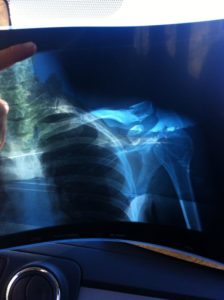

BUESCAS – Marc de Maar heeft zijn voorliefde voor het rijden van mountainbikemarathons moeten bekopen met een sleutelbeenbreuk. De coureur van Roompot, een van de weinige Nederlandse wegrenners die ook regelmatig op de mountainbike koerst, ging afgelopen weekeinde onderuit bij de Quebrantahuesos MTB Marathon in het Spaanse Buescas.